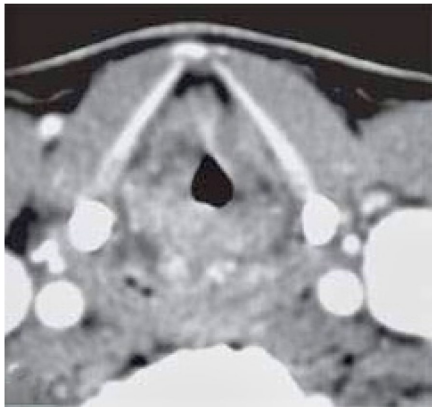

24岁女性患者因持续6周的发音困难(dysphonia)和吞咽痛(odynophagia)就诊,有4年高功率电子烟使用史。喉镜检查可见声门上区和声门区大面积黏膜坏死伴溃疡形成。

病例2:男性患者气道危机

30岁男性在5年电子烟使用后出现进行性喘鸣(stridor),组织病理显示非特异性坏死性炎症。